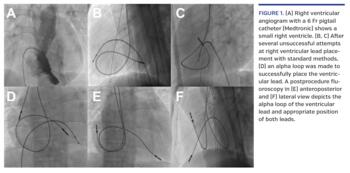

A 22-year-old male patient, diagnosed with non-familial idiopathic restrictive cardiomyopathy on the basis of symptoms, transthoracic echocardiogram, cardiac magnetic resonance imaging, cardiac catheterization, and genetic testing, presented with recurrent episodes of syncope. A 24-hour ambulatory monitoring revealed high-grade atrioventricular block. A dual-chamber permanent pacemaker implantation with DDDR pacing was planned. After uneventful right axillary venous punctures, several attempts to place an active fixation ventricular lead (Biotronik) were unsuccessful (Figures 1B and 1C) as the lead failed to prolapse across the tricuspid valve due to the hugely dilated right atrium and a small right ventricle (Figure 1A). An alpha loop was made in the right atrium to negotiate the tricuspid valve and enhance the lead stability (Figure 1D). After the confirmation of appropriate thresholds and impedance, the lead was screwed at the ventricular apex. The positioning of the right atrial lead was uneventful. A postprocedure on-table fluoroscopy (Figures 1E and 1F) and x-ray after 24 hours depicted the alpha loop and appropriate lead position. At 3-month follow-up, the patient was symptomatically better and device interrogation showed stable lead parameters. High-grade and complete heart block commonly occurs in adult patients with restrictive cardiomyopathy, and requires aggressive monitoring and prophylactic pacemaker/defibrillator. There are limited data on the procedural details of pacemaker implantation in this group of patients, and as reported, special maneuvers may be required for ventricular lead placement.